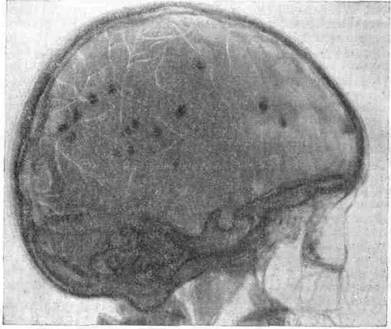

Рентгенологически в костях пальцев рук и ног определяются периостальные утолщения и центральные полости остеопороза. Описаны изменения в большеберцовой и малоберцовой костях. При рентгенографии черепа определяются множественные петрификаты небольших размеров, которые чаще всего локализуются в области III и боковых желудочков, но могут располагаться и в корковом веществе мозга, в мозжечке (рис. 4).

Рис. 4.

Краниограмма черепа при туберозном склерозе.

При мозжечковой локализации петрификатов на рентгенограмме могут быть двухконтурные тени, по ходу извилин мозжечка, напоминающие таковые при болезни Штурге–Вебера, однако они встречаются крайне редко.